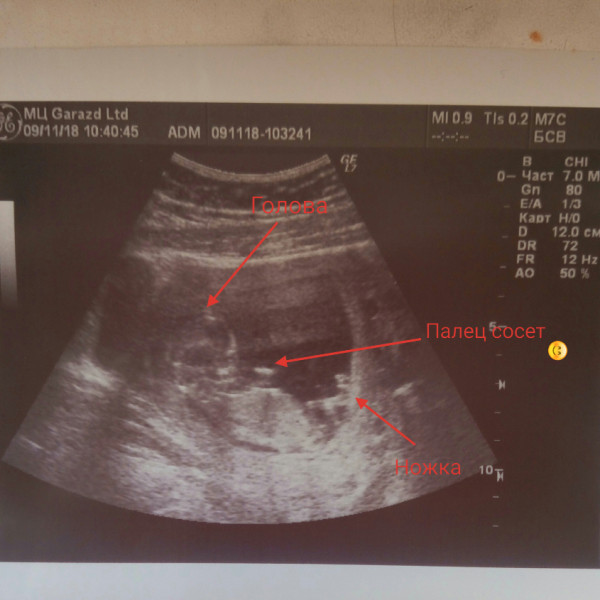

Ваш ребенок растет и развивается: отмечаются первые дыхательные движения, но сейчас это просто тренировка диафрагмы, голосовая щель сомкнута, и по-настоящему дышать он сможет лишь после появления на свет. У малыша продолжают отвердевать кости, закладываются ребра. На пальчиках появляются отпечатки – уникальный узор, который сохранится на всю жизнь.

Малыш: Ваш малыш быстро растет! Глаза принимают правильное положение, лодыжки и запястья сформированы, и, хотя голова все еще непропорционально велика, остальная часть тела начинает подтягиваться. На этой неделе кишечник вашего ребенка вернулся на свое место. Ваш ребенок проглатывает амниотическую жидкость и всасывает ее в свое тело. Позвоночник ребенка может сгибаться, что облегчает большие движения. Если вы думаете, что у вас могут быть близнецы, УЗИ на этой неделе может это подтвердить!

Они покрыты очень тонкими волосами, называемыми лануго, которые обычно выпадают при рождении. Брови и волосы на макушке начинают расти, кости становятся тверже, и ребенок может даже сосать палец. Сейчас их органы полностью сформированы и будут продолжать расти. Возможно, на этой неделе вы сможете определить пол ребенка с помощью УЗИ высокого разрешения!

Пальцы рук и ног вашего ребенка хорошо очерчены; у них формируются веки, брови, ресницы, ногти и волосы. Зубы и кости становятся более плотными. Ваш ребенок может даже сосать палец, зевать, потягиваться и корчить рожицы.